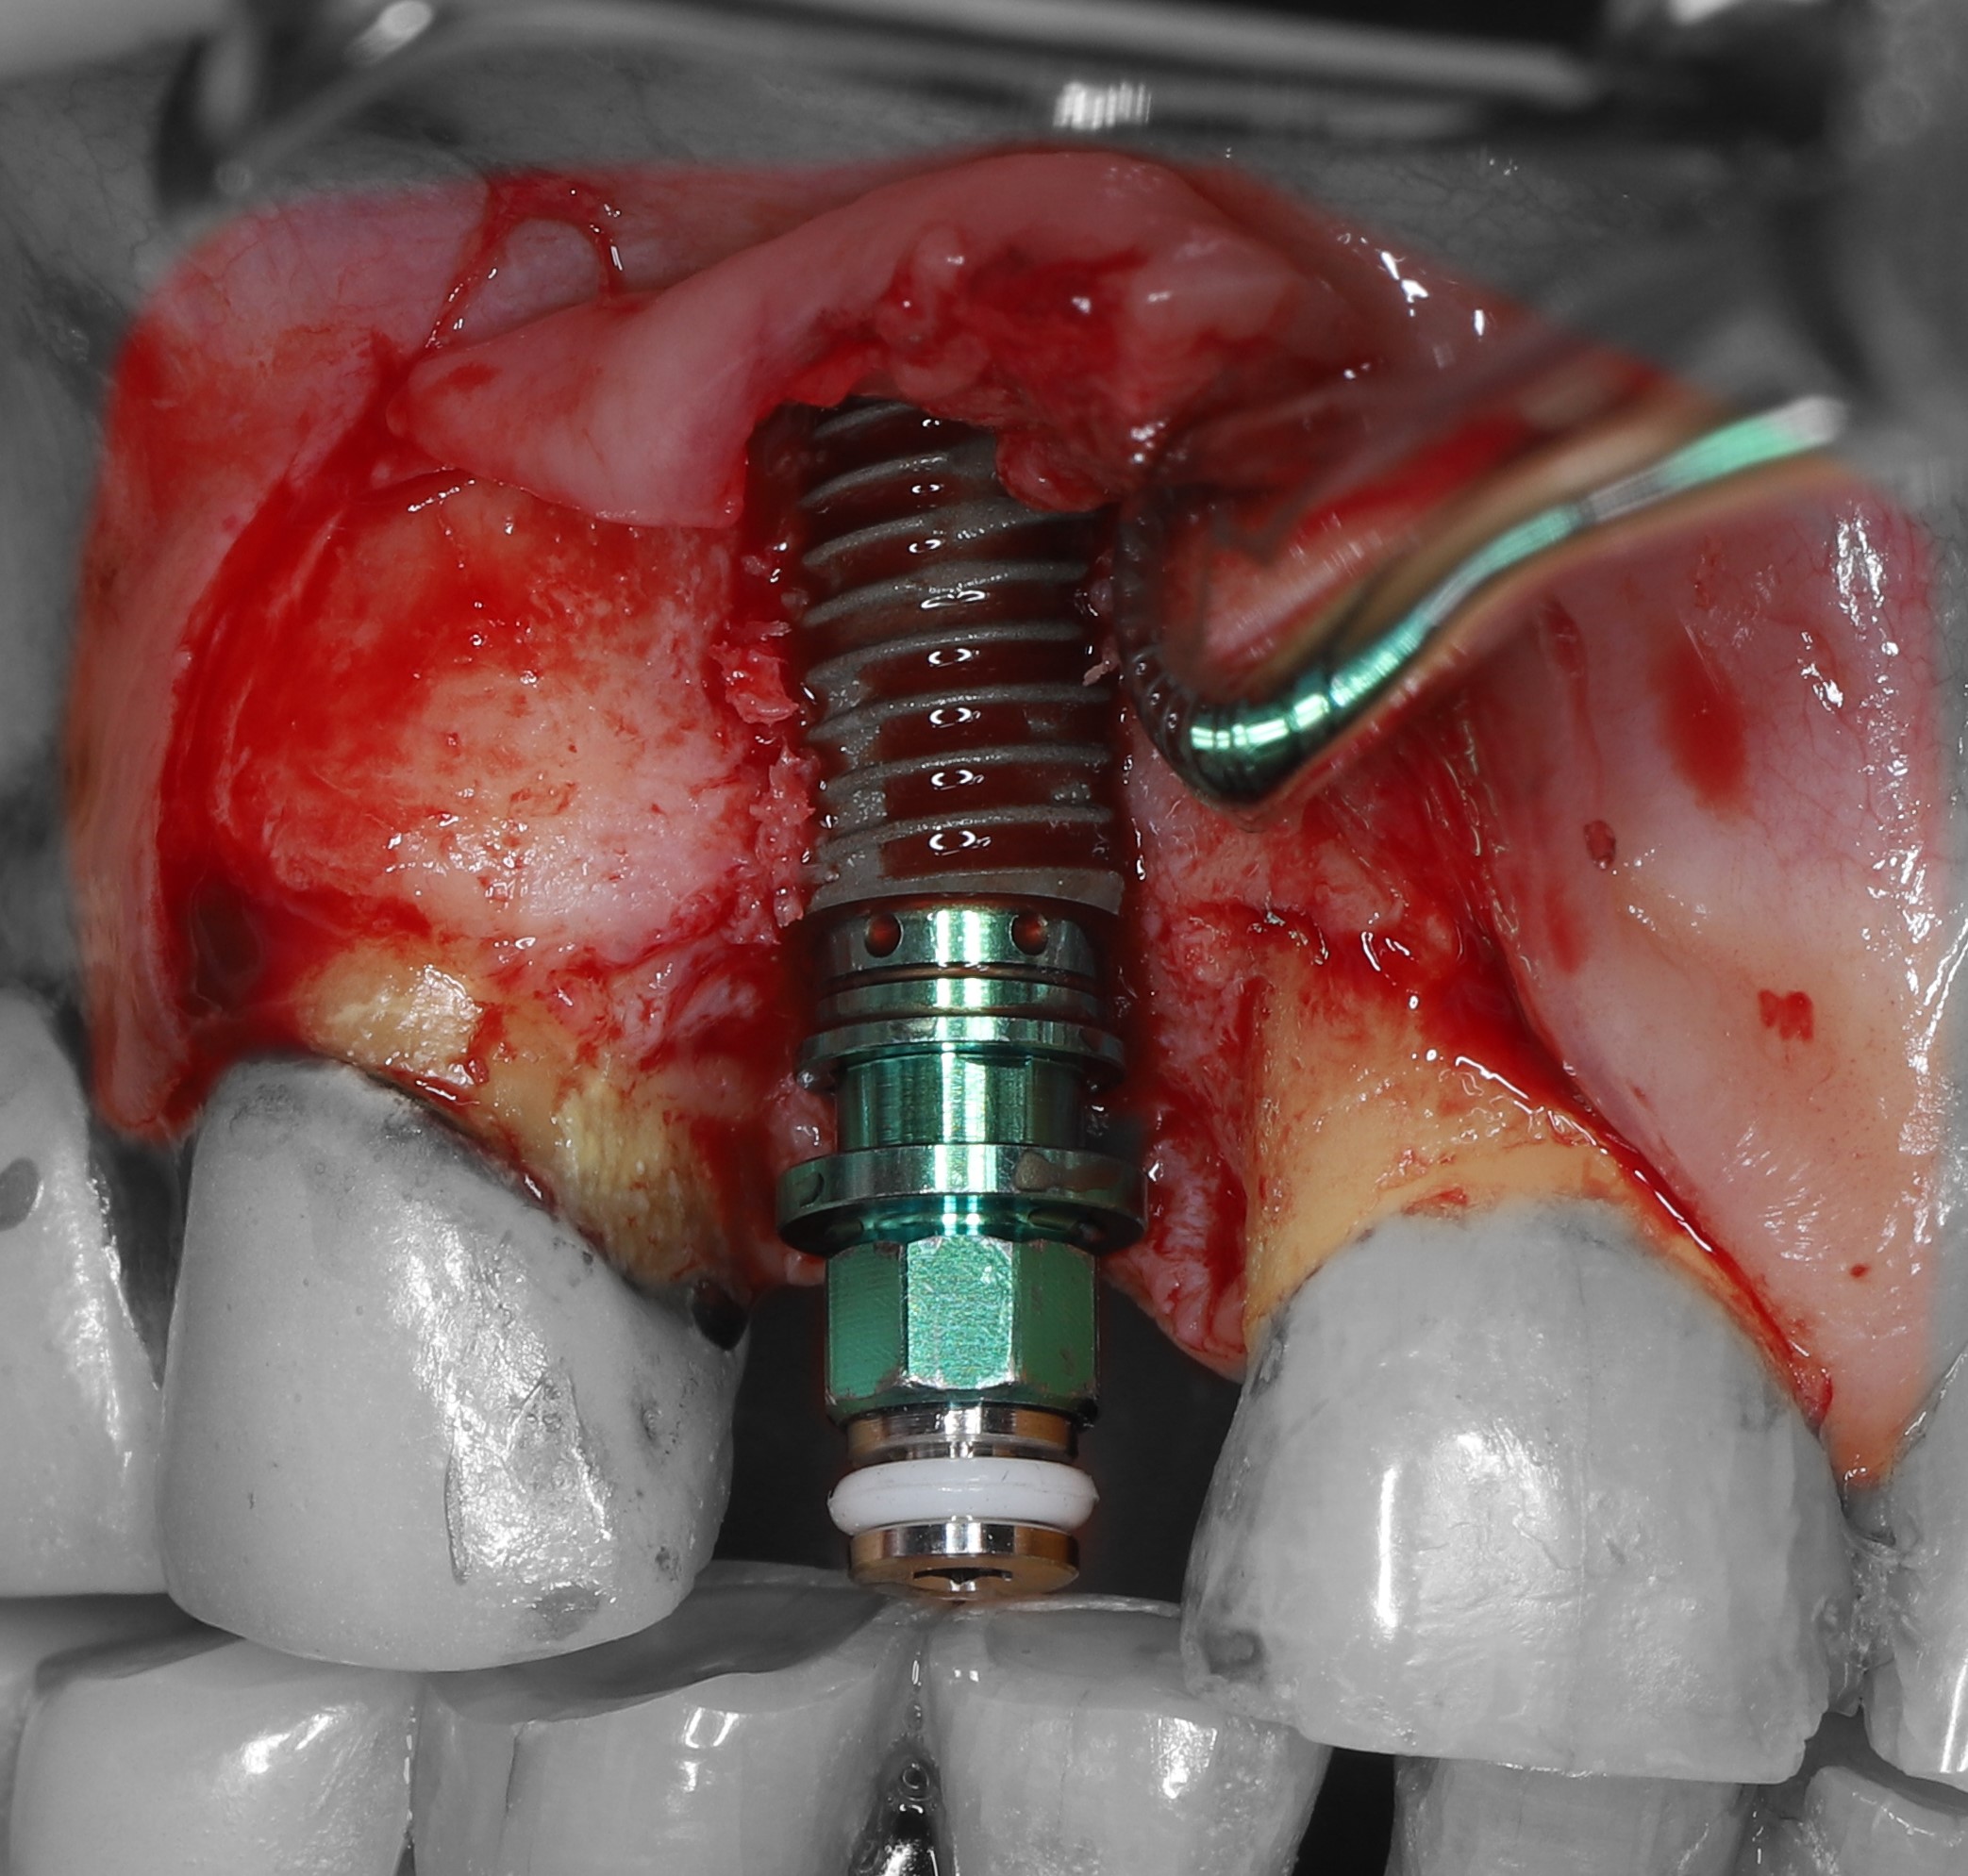

3) Проведена остеотомия имплантантного ложа.

4) Установлен имплантат Osstem 4.5*10 мм., визуализируется выраженная дегистенция имплантата в области вестибулярной костной стенки.

6) Костный графт был фиксирован в области вестибулярного дефекта с помощью прижатия 2-мя пинами.